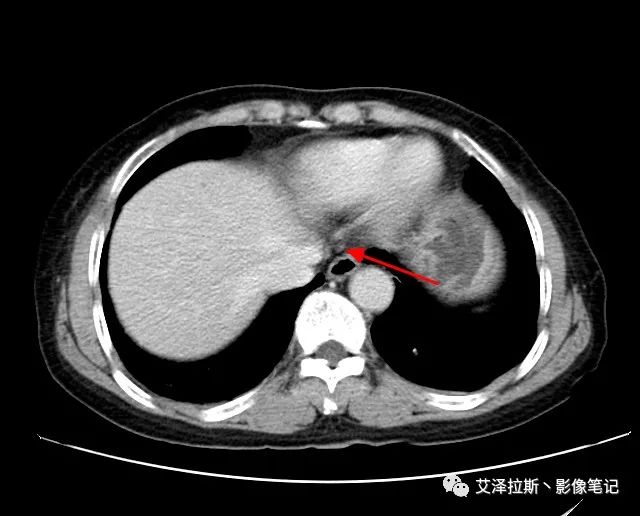

圖1 平掃+增強各期

【影像所見】 胃竇部狹窄,胃壁環形增厚,小彎側見一巨大潰瘍,周圍伴“環堤征”,漿膜面不完整,胃周脂肪見網格狀條索影,病灶與肝臟左葉、胰腺鉤突脂肪間隙消失,增強掃描病灶明顯強化。引流區內約15個區域淋巴結受累。

【診斷意見】 胃竇部胃癌(T4N3期) 該病例腫塊突破漿膜層,與肝臟左葉、胰腺鉤突分界不清,脂肪界面消失,定為T4期; 受累及的淋巴結為15個區域,定為N3; 有無遠處轉移尚不明確,所以M期暫時無法確定。